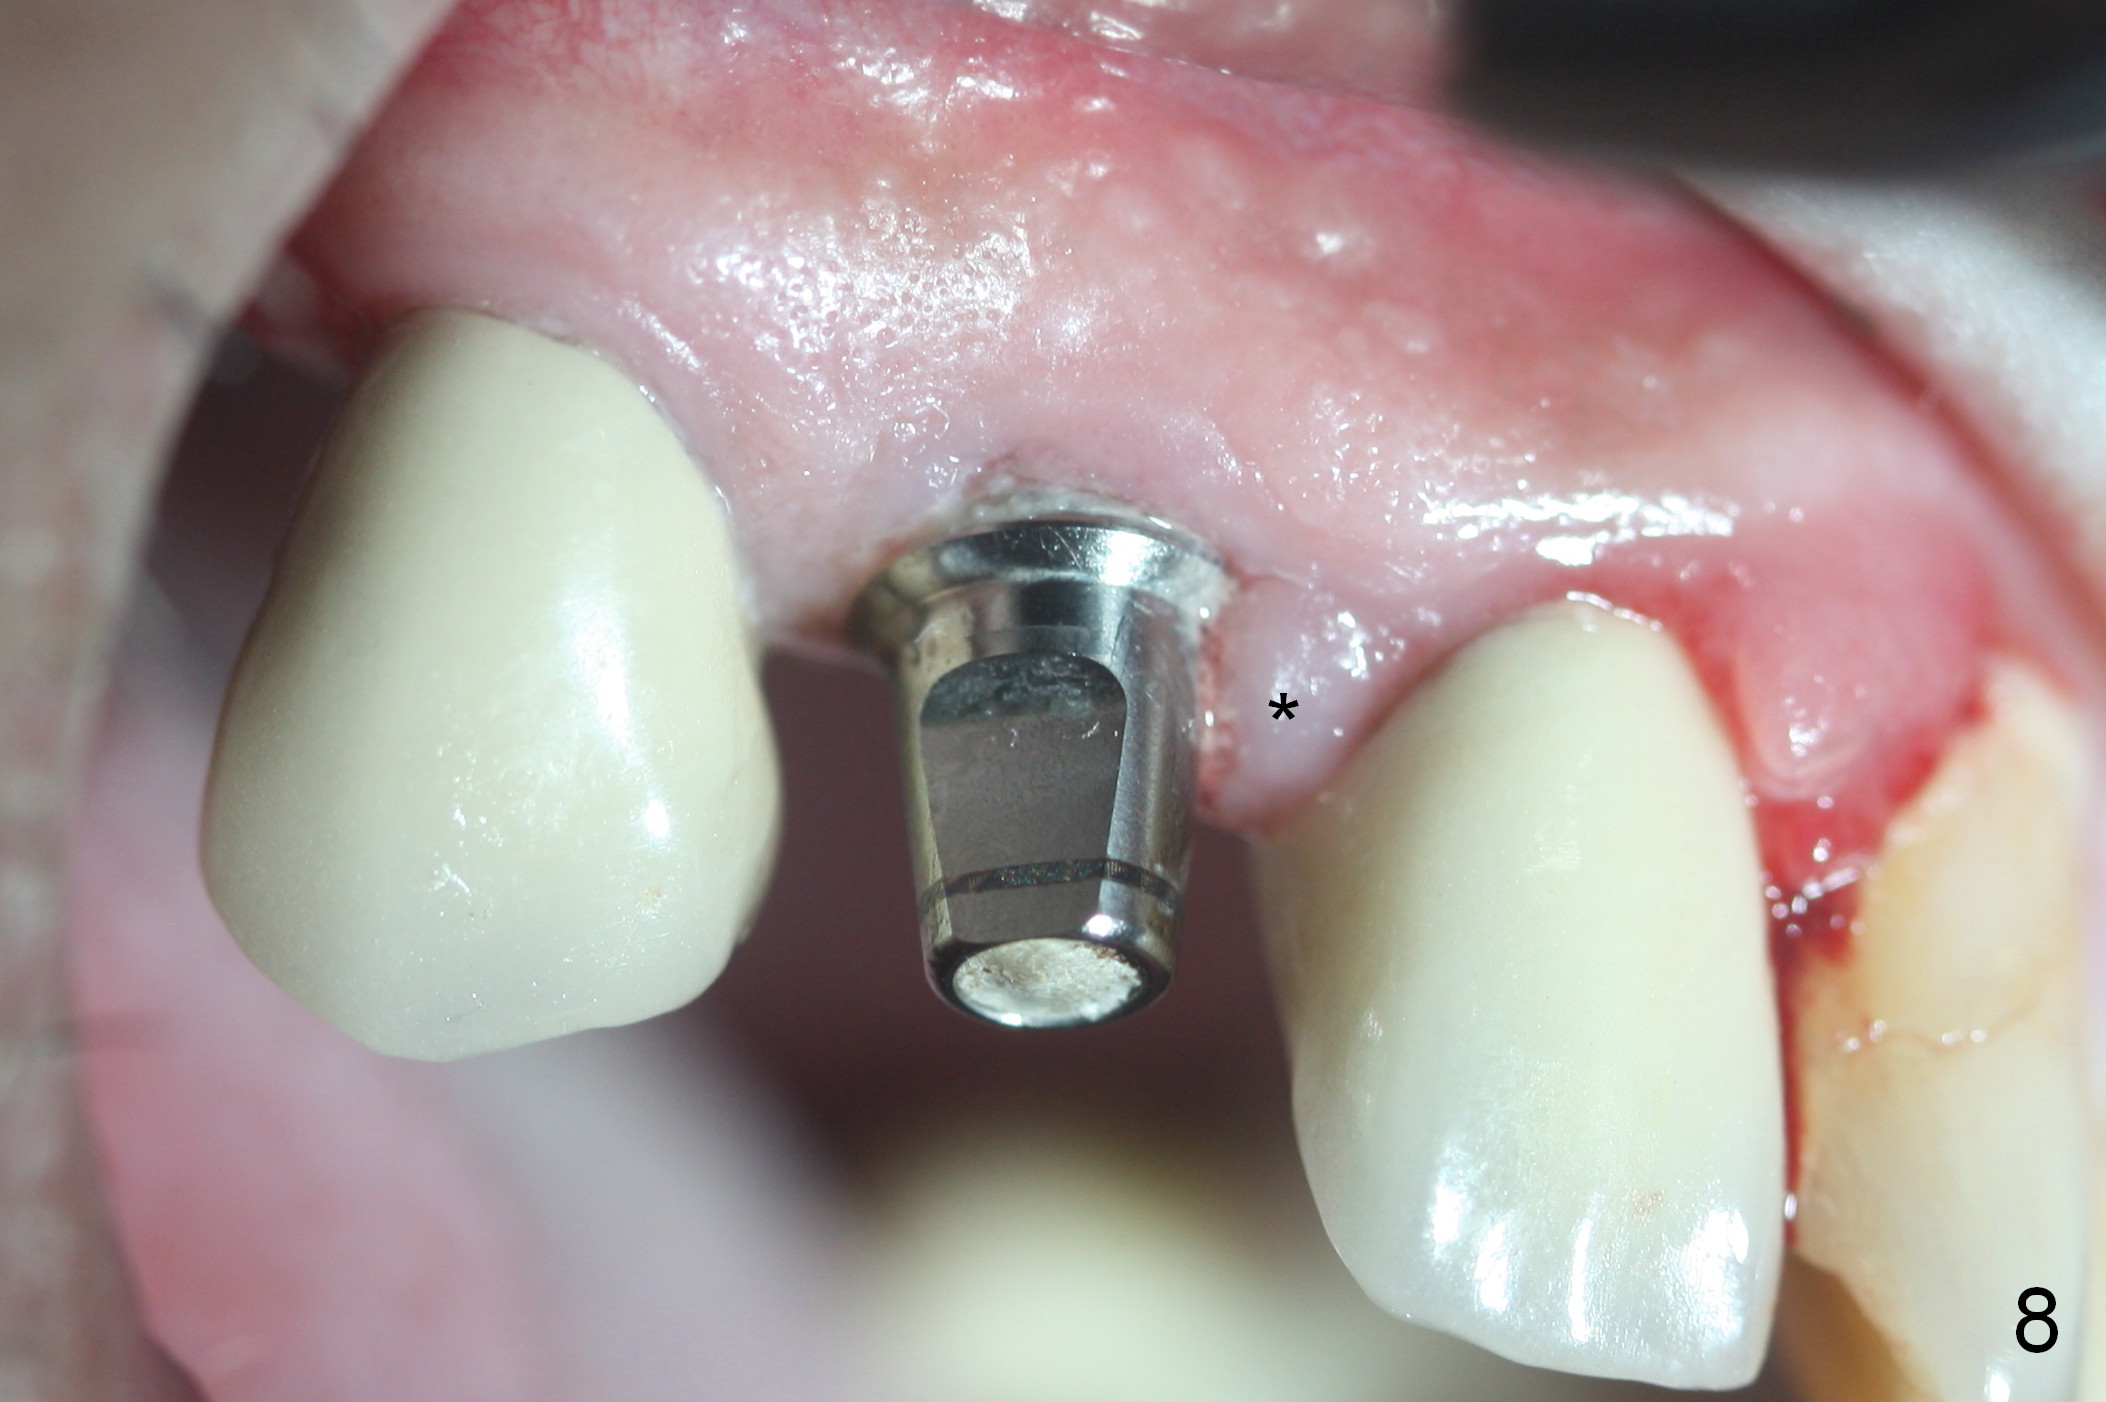

Three months postop, the provisional is dislodged (Fig.7-9). The mesial gingiva is hypertrophic buccally (Fig.8 *) and lingually (Fig.9 *). There appears to biologic width violation (Fig.5). The abutment should be changed to the one with smaller in diameter and longer in cuff (4.5x5(4) mm) with the buccal margin reduction.

Six days post provisional reline, the mesial papilla erythema has subsided substantially; the abutment is changed to 4.5x5(2) with Diode gingivectomy (Fig.10-12).